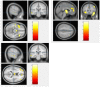

Methods: In this study, we recruited 72 patients with schizophrenia and 74 healthy individuals matched by age and sex to investigate the structural brain changes that may serve as prognostic biomarkers, indicating evidence of neural dysfunction underlying schizophrenia and subsequent cognitive and behavioral deficits. We used voxel-based morphometry (VBM) to determine these changes in the three tissue structures: the gray matter (GM), white matter (WM), and cerebrospinal fluid (CSF). For both image processing and statistical analysis, we used statistical parametric mapping (SPM).

Results: Our results show that patients with schizophrenia exhibited a significant volume reduction in both GM and WM. In particular, GM volume reductions were more evident in the frontal, temporal, limbic, and parietal lobe, similarly the WM volume reductions were predominantly in the frontal, temporal, and limbic lobe. In addition, patients with schizophrenia demonstrated a significant increase in the CSF volume in the left third and lateral ventricle regions.